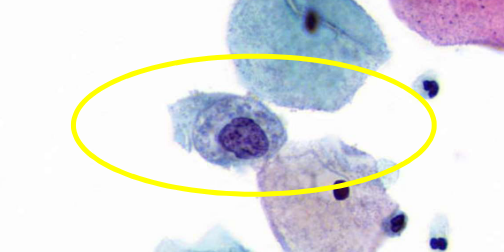

baseline cells

endocervical cells